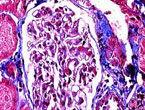

Berger病是以反覆發作性肉眼或鏡下血尿,腎小球系膜細胞增生,基質增多,伴廣泛IgA沉積為特點的原發性腎小球疾病。1968年Berger首先描述本病,故又稱Berger病。此外,又被稱為IgA-IgG系膜沉積性腎炎和IgA系膜性腎炎等。

實驗室診斷:鏡下血尿者,尿紅細胞以畸形者為主。約50%患者血清IgA增高,但與病情活動無關。血清IgA中λ輕鏈濃度增高。尿免疫球蛋白測定無特殊意義。血補體成分大多正常。某些補體成分或因子可能減少,主要見於有家族高發傾向病人中,但不具有診斷價值。約半數病人IgA-纖維連線蛋白聚集物測定值可有一過性增高,雖然有助於與其他腎病鑑別,但其與本病活動無關,故並無診斷價值。10%~15%病人可有IgA循環免疫複合物增高,32%病人有IgA類風濕因子水平增高。多項免疫學指標,包括病毒和食物抗原、抗體、T細胞亞群、HLA位點抗原等測定結果可有改變,但均無診斷價值。50%病人前臂掌側皮膚活檢中可見毛細血管內有IgA和C3等沉積。